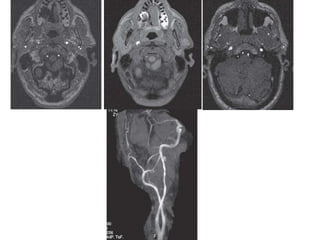

Initial screening test is noninvasive , either DS or MRA.

TOF MRA is less sensitive DS (75%Vs 87%) but more specific (88%Vs

46%).

Concordance in TOF and DS is more sensitive(96%) and specific

(85%) than either test alone.(Johnston, and Goldstein et al 2001)

2D TOF MRA over estimates the degree of stenosis.

3D TOF MRA is less likely to overestimate stenosis.

Combination of 2D and 3D TOF MRA results in greater specificity.

 ‘FLOW GAP’- segmental dropout , When the stenosis is more than

70%. ( Heiserman JE et al 1996)

3D CEMRA have greater anatomical coverage in terms of surface

morphology, carotid bifurcation, near occlusion

3D CE MRA is more sensitive(94.6% vs 91.2%) and specific ( 88.3%vs

91.9%) than TOF MRA for high grade ICA stenosis.

Carotid atherosclerotic narrowing

Carotid stenosis

2D TOF MRA 3D TOF MRA DSA

Carotid

stenosis

CE-MRA

3D TOF-

MRA

Basilar artery stenosis

3D TOF-MRA CTA DSA